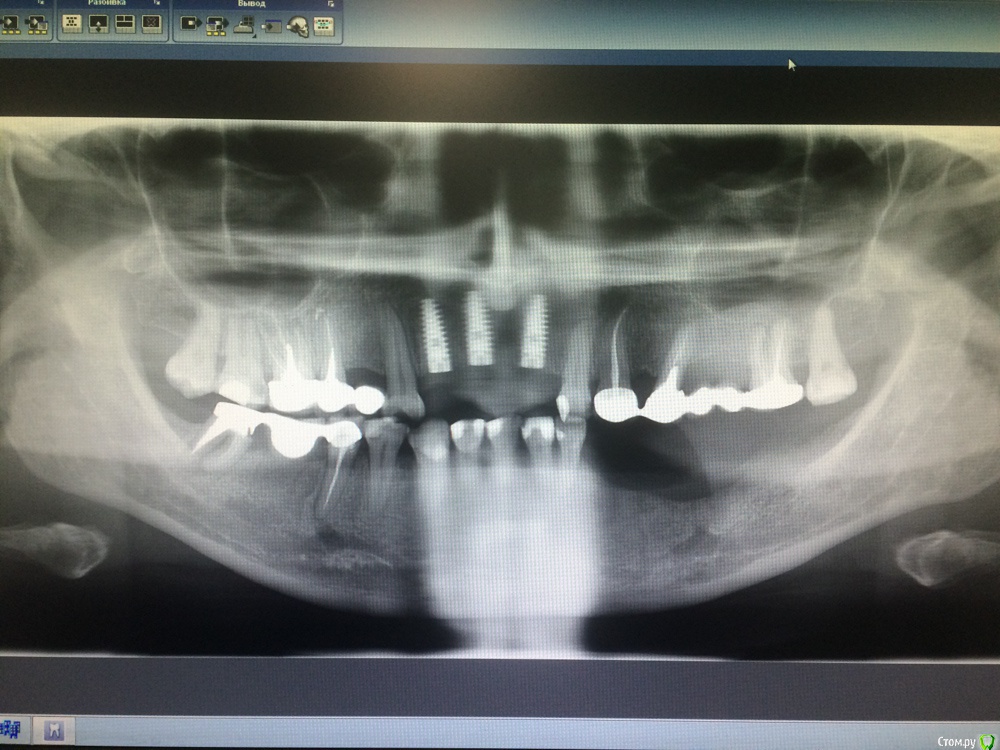

Игнатович Опубликовано 2 марта, 2015 Поделиться Опубликовано 2 марта, 2015 Доброго времени суток. Сам я ортопед. Вашему вниманию представляю пару снимков и хочу спросить совета: что делать с левой стороной нижней челюсти???Планируется замена МК конструкций на верхней челюсти, изготовление ДЦ коронок на инд абатментах на 11,21,22, ламинаты-полукоронки-коронки на фронт верх и низ... Мост на 45-47 нас покинет, так же, как и сам 47. Больше всего волнует низ левая сторона, атрофия значительная, узкий альвеолярный гребень, зубы удалены около года. Для пациентки более предпочтительна несъёмная конструкция.Варианты, которые приходят в голову:-костная пластика и имплантация двухэтапными имплантатами? (где брать костные блоки и мягкие ткани, гарантирован ли результат?? и через сколько после операции можно будет протезироваться?) -имплантация одноэтапными имплантатами и немедленная нагрузка металлопластмассовой шиной (но какова получится эстетика и не вынесет ли она коронки вместе с имплантатами)???-съемник (как вариант бюгельный ацеталовый)???СПАСИБО!) Ссылка на комментарий

Dr.Zoom Опубликовано 7 марта, 2015 Поделиться Опубликовано 7 марта, 2015 В 3ем сегмете или съемник или аугментация без временного протезирования на пол-годика))) Ссылка на комментарий

bugel Опубликовано 7 марта, 2015 Поделиться Опубликовано 7 марта, 2015 Я бы ещё 5 и 7 на удаление отправил справа. Ссылка на комментарий